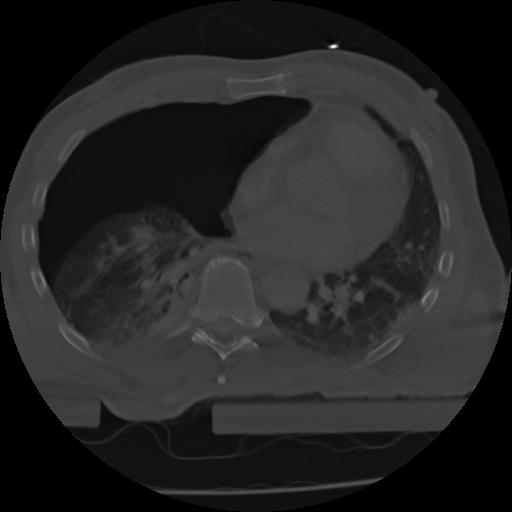

21 ANGIO,CE,Axial,3.0,ANGIO,,